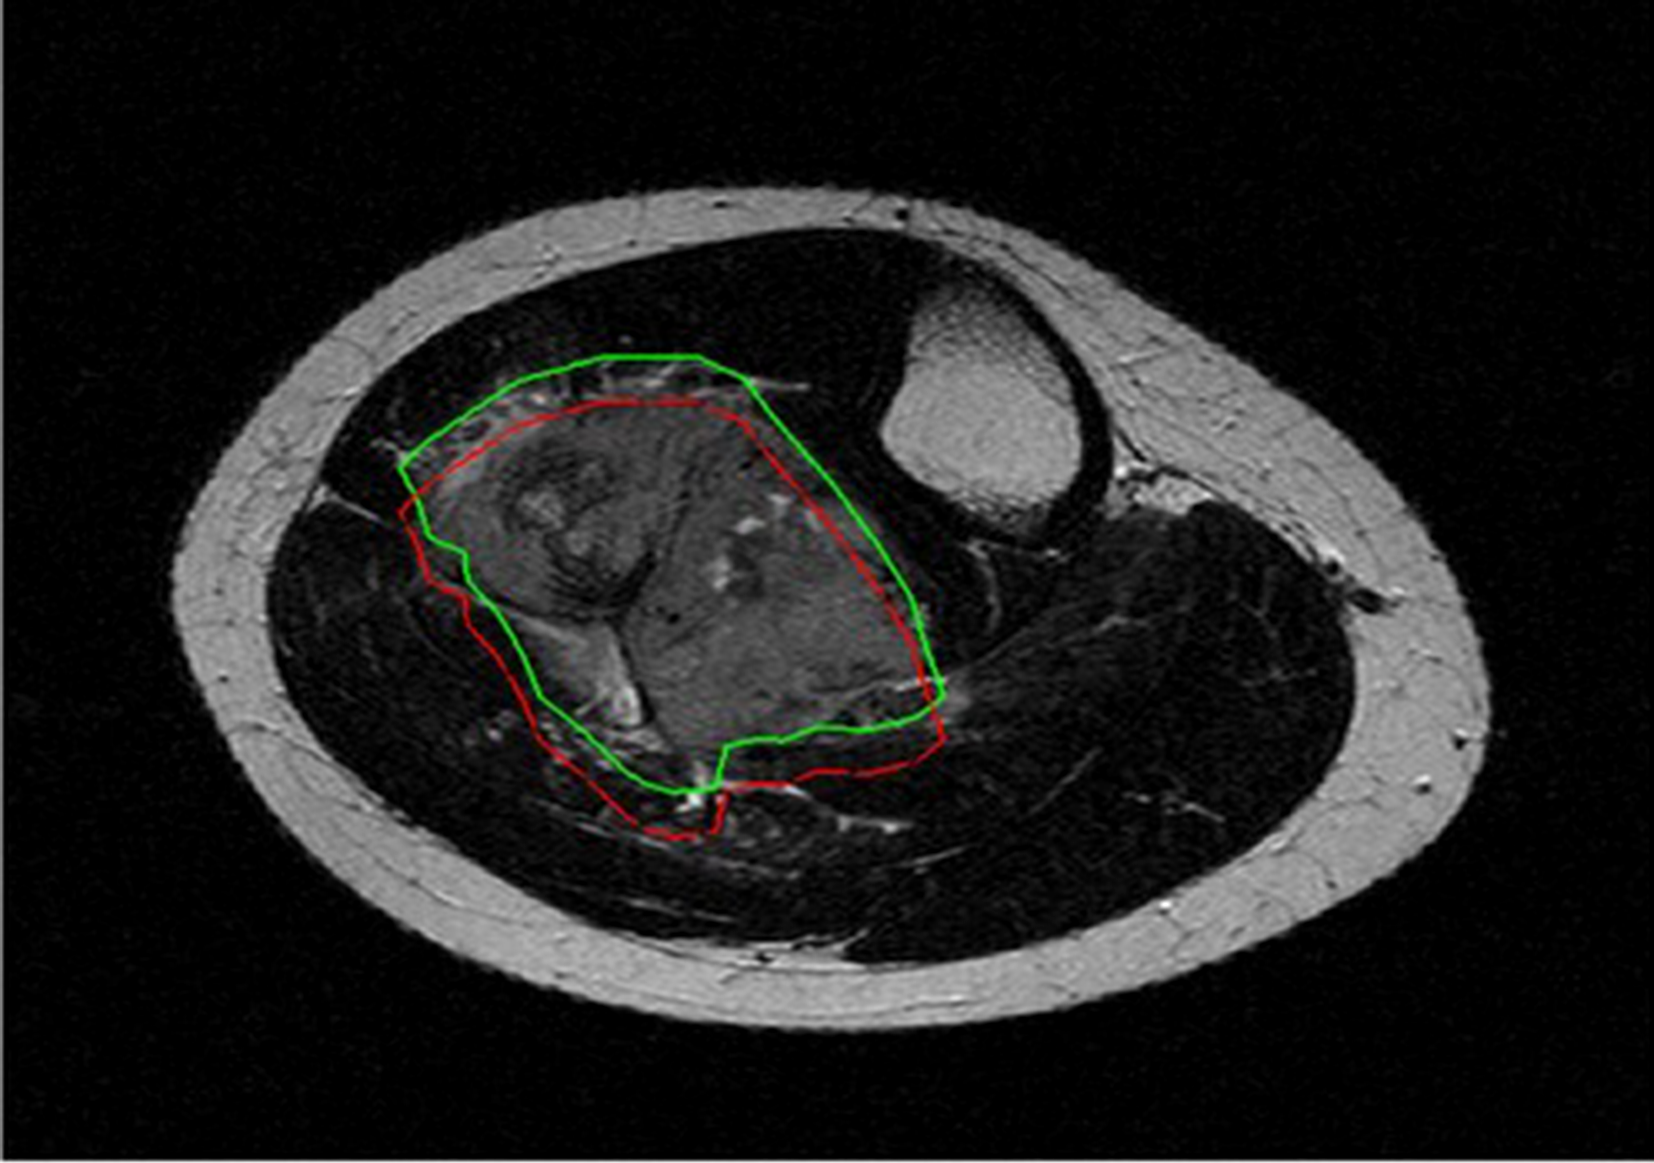

All DICOM images were extracted and imported to the freely available, open-source software ITK-SNAP (v3.8) (12) for segmentation. On T1-weighted and T2-weighted MRI, manual segmentations were obtained by drawing both 2D regions of interest (ROIs) along tumour borders on the slice showing the largest tumour area and 3D ROIs including the whole tumour volume. The “polygon mode” ITK-SNAP tool was used for all segmentations (Figure 1). A musculoskeletal radiologist performed all segmentations. The radiologist knew the study would deal with Ewing sarcoma but was blinded to any information regarding disease course.

Figure 1 On the slice showing the largest tumor area (A), 2D manual segmentation was obtained by drawing a polygonal region of interest (B) to include the whole tumor area (C). The same procedure was repeated slice by slice to obtain 3D segmentation including the whole tumor volume.